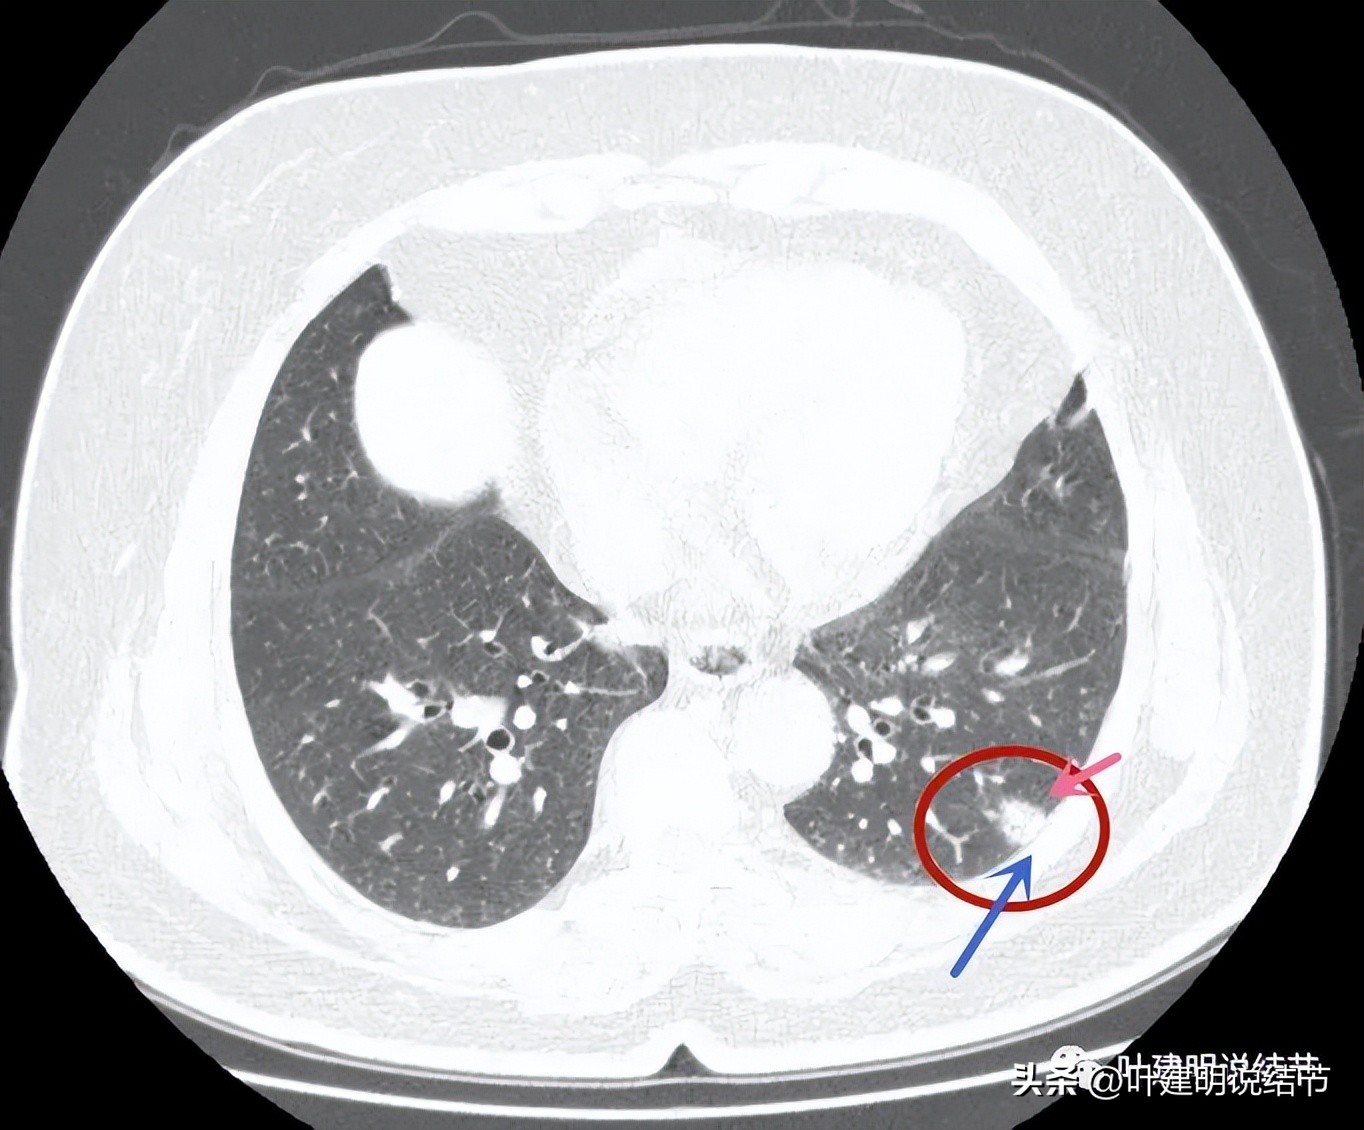

病灶表面不是很平整,整体密度较高,胸膜间隙征存在。

与胸壁接触的面较宽,余边也平直。

病灶密度整体较高

边缘部分